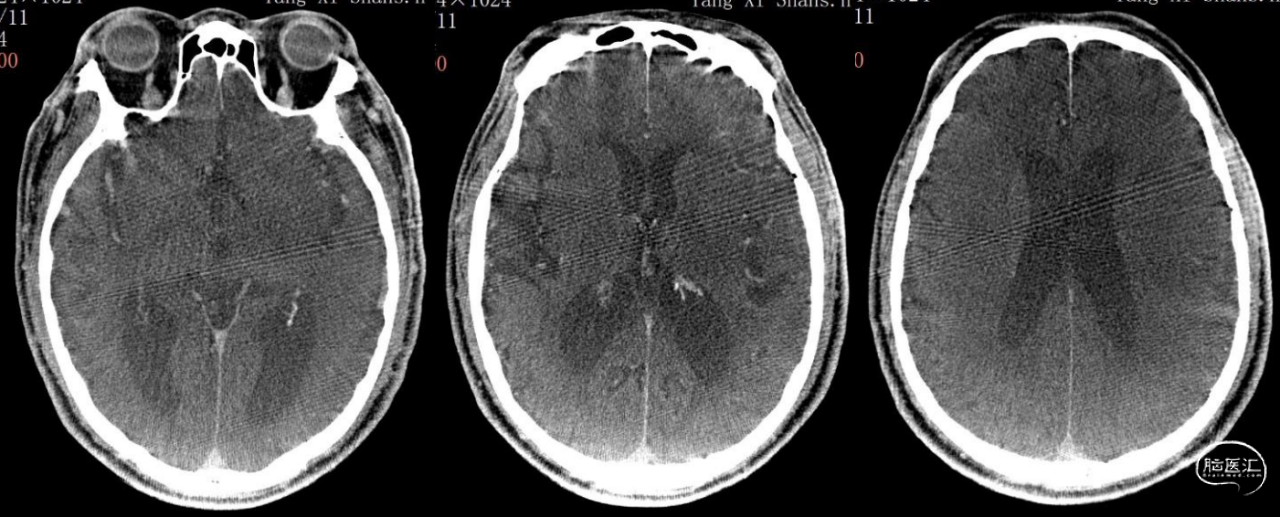

现病史:患者 3 小时前睡醒后(距最后正常时间为 7 小时)被家属发现不能言语,右侧肢体无自主活动,无意识障碍、肢体抽搐、大小便失禁等症状,急诊评估 NIHSS 评分 17 分,行头部 CT 排除出血(图 1),绿道 DWI+MRA 示左侧大脑半球多发急性梗死灶,左侧大脑中动脉 M1 分叉前闭塞,远端显影较淡(图 2)。向家属告知病情及静脉溶栓、急诊取栓风险、获益,家属表示知情理解,同意直接取栓治疗。

图 1: 2023.10.22 CT 平扫:脑内多发腔隙性脑梗死。ASPECT:10 分